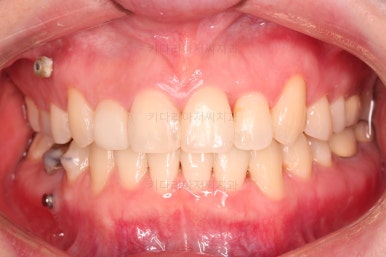

부산치과교정 전후사진을 비교해 볼게요.

발치교정이라고 입매가 들어간 것도 아니고 오히려 더 예뻐졌죠?

중심선도 원하시는만큼 갖추었고, 가지런한 느낌도 좋고요.

21개월만에 전반적으로 매우 만족할만한 치료 결과를 얻었습니다.

이상 미니스크류와 비대칭적 발치를 통해 중심선(정중선, 중앙선)의 비대칭과 덧니를 개선한 부산치과교정 치료사례였습니다.